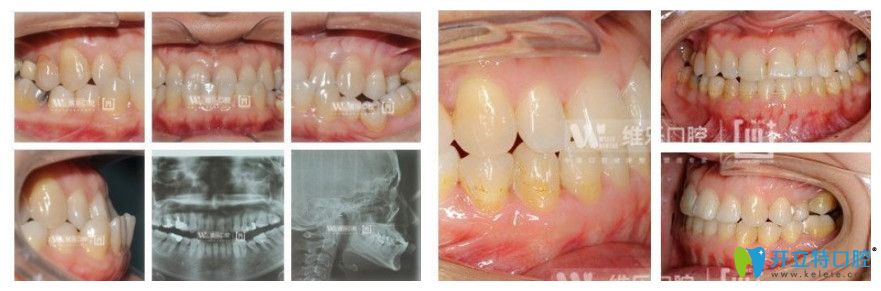

案例三:38歲女性地包天矯正

牙齒問(wèn)題:上頜后縮,下頜前突,全列牙反頜,咬合不佳。

矯正方式:金屬自鎖托槽矯正

維樂(lè)口腔8歲女性地包天矯正前后對(duì)比圖

顧客感言:通過(guò)矯正后,牙齒反頜解除,咬合問(wèn)題解決,面型得到明顯改善。